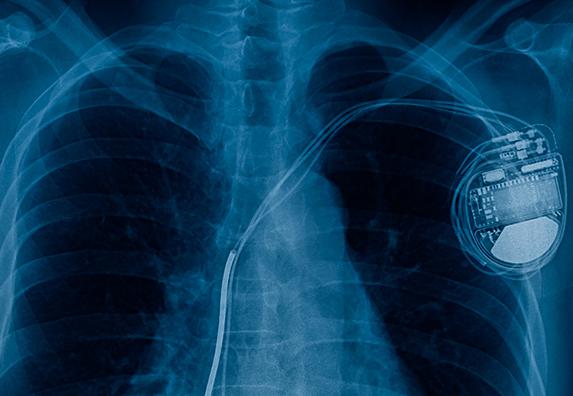

IMPLANTABLE TECHNOLOGY

Medical devices that are implanted into the body are an area of differentiated capability for WELEXON. Our Salem site is a leader in medical embedded ceramic components (distributed to discrete passives and active components). With tight tolerances for finer lines and spaces, WELEXON delivers technology solutions with a significant impact on the people who rely on them to maintain and improve their quality of life.

• Pacemakers/defibrillators